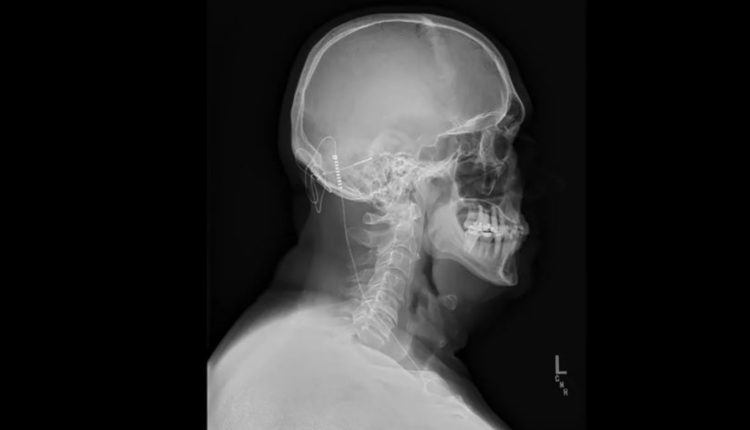

فقد عرض عليه جرّاح الأعصاب أندريه ماتشادو في كليفلاند كلينيك التطوع ليكون أول شخص في العالم يزرع جهازاً يبلغ حجمه 103 ميليمترات، في الدماغ والصدر ليستعيد الوظائف التي تضررت بسبب الجلطة.

فقد عمل فريق من الباحثين على تطوير هذه التقنية التي تقضي باستخدام جهاز لتحفيز الجزء المسؤول عن حركة اليدين والمشي والتوازن في الدماغ، على العمل بشكل طبيعي، حتى في الأجزاء التي تضررت بسبب الجلطة. هذه التقنية تقضي بزرع إلكترود في أسفل الدماغ من الخلف ويتصل بسلك مع جهاز زرع تحت الجلد في الصدر.